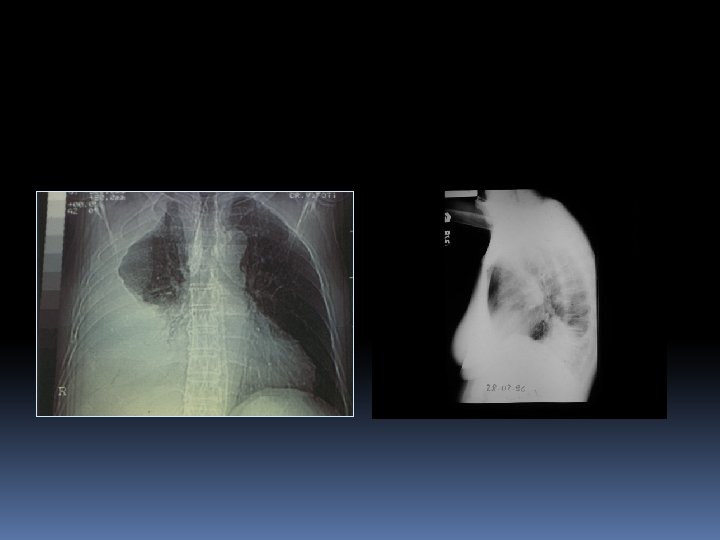

EMPIEMA PLEURICO Diagnosi Esame Radiografico del torace: mette in evidenza un’ipodiafania dell’emitorace interessato (con possibile margine laterale che si innalza fino all’ascella); possibile la presenza di livelli idroaerei per produzione di gas da parte dei batteri. In laterale può evidenziarsi, negli empiemi a sede postero-laterale, il segno tipico di un’opacità posteriore a forma di D -invertita (pregnant lady sign). Negli empiemi saccati l’ipodiafania appare come un’opacità simil-parenchimale.